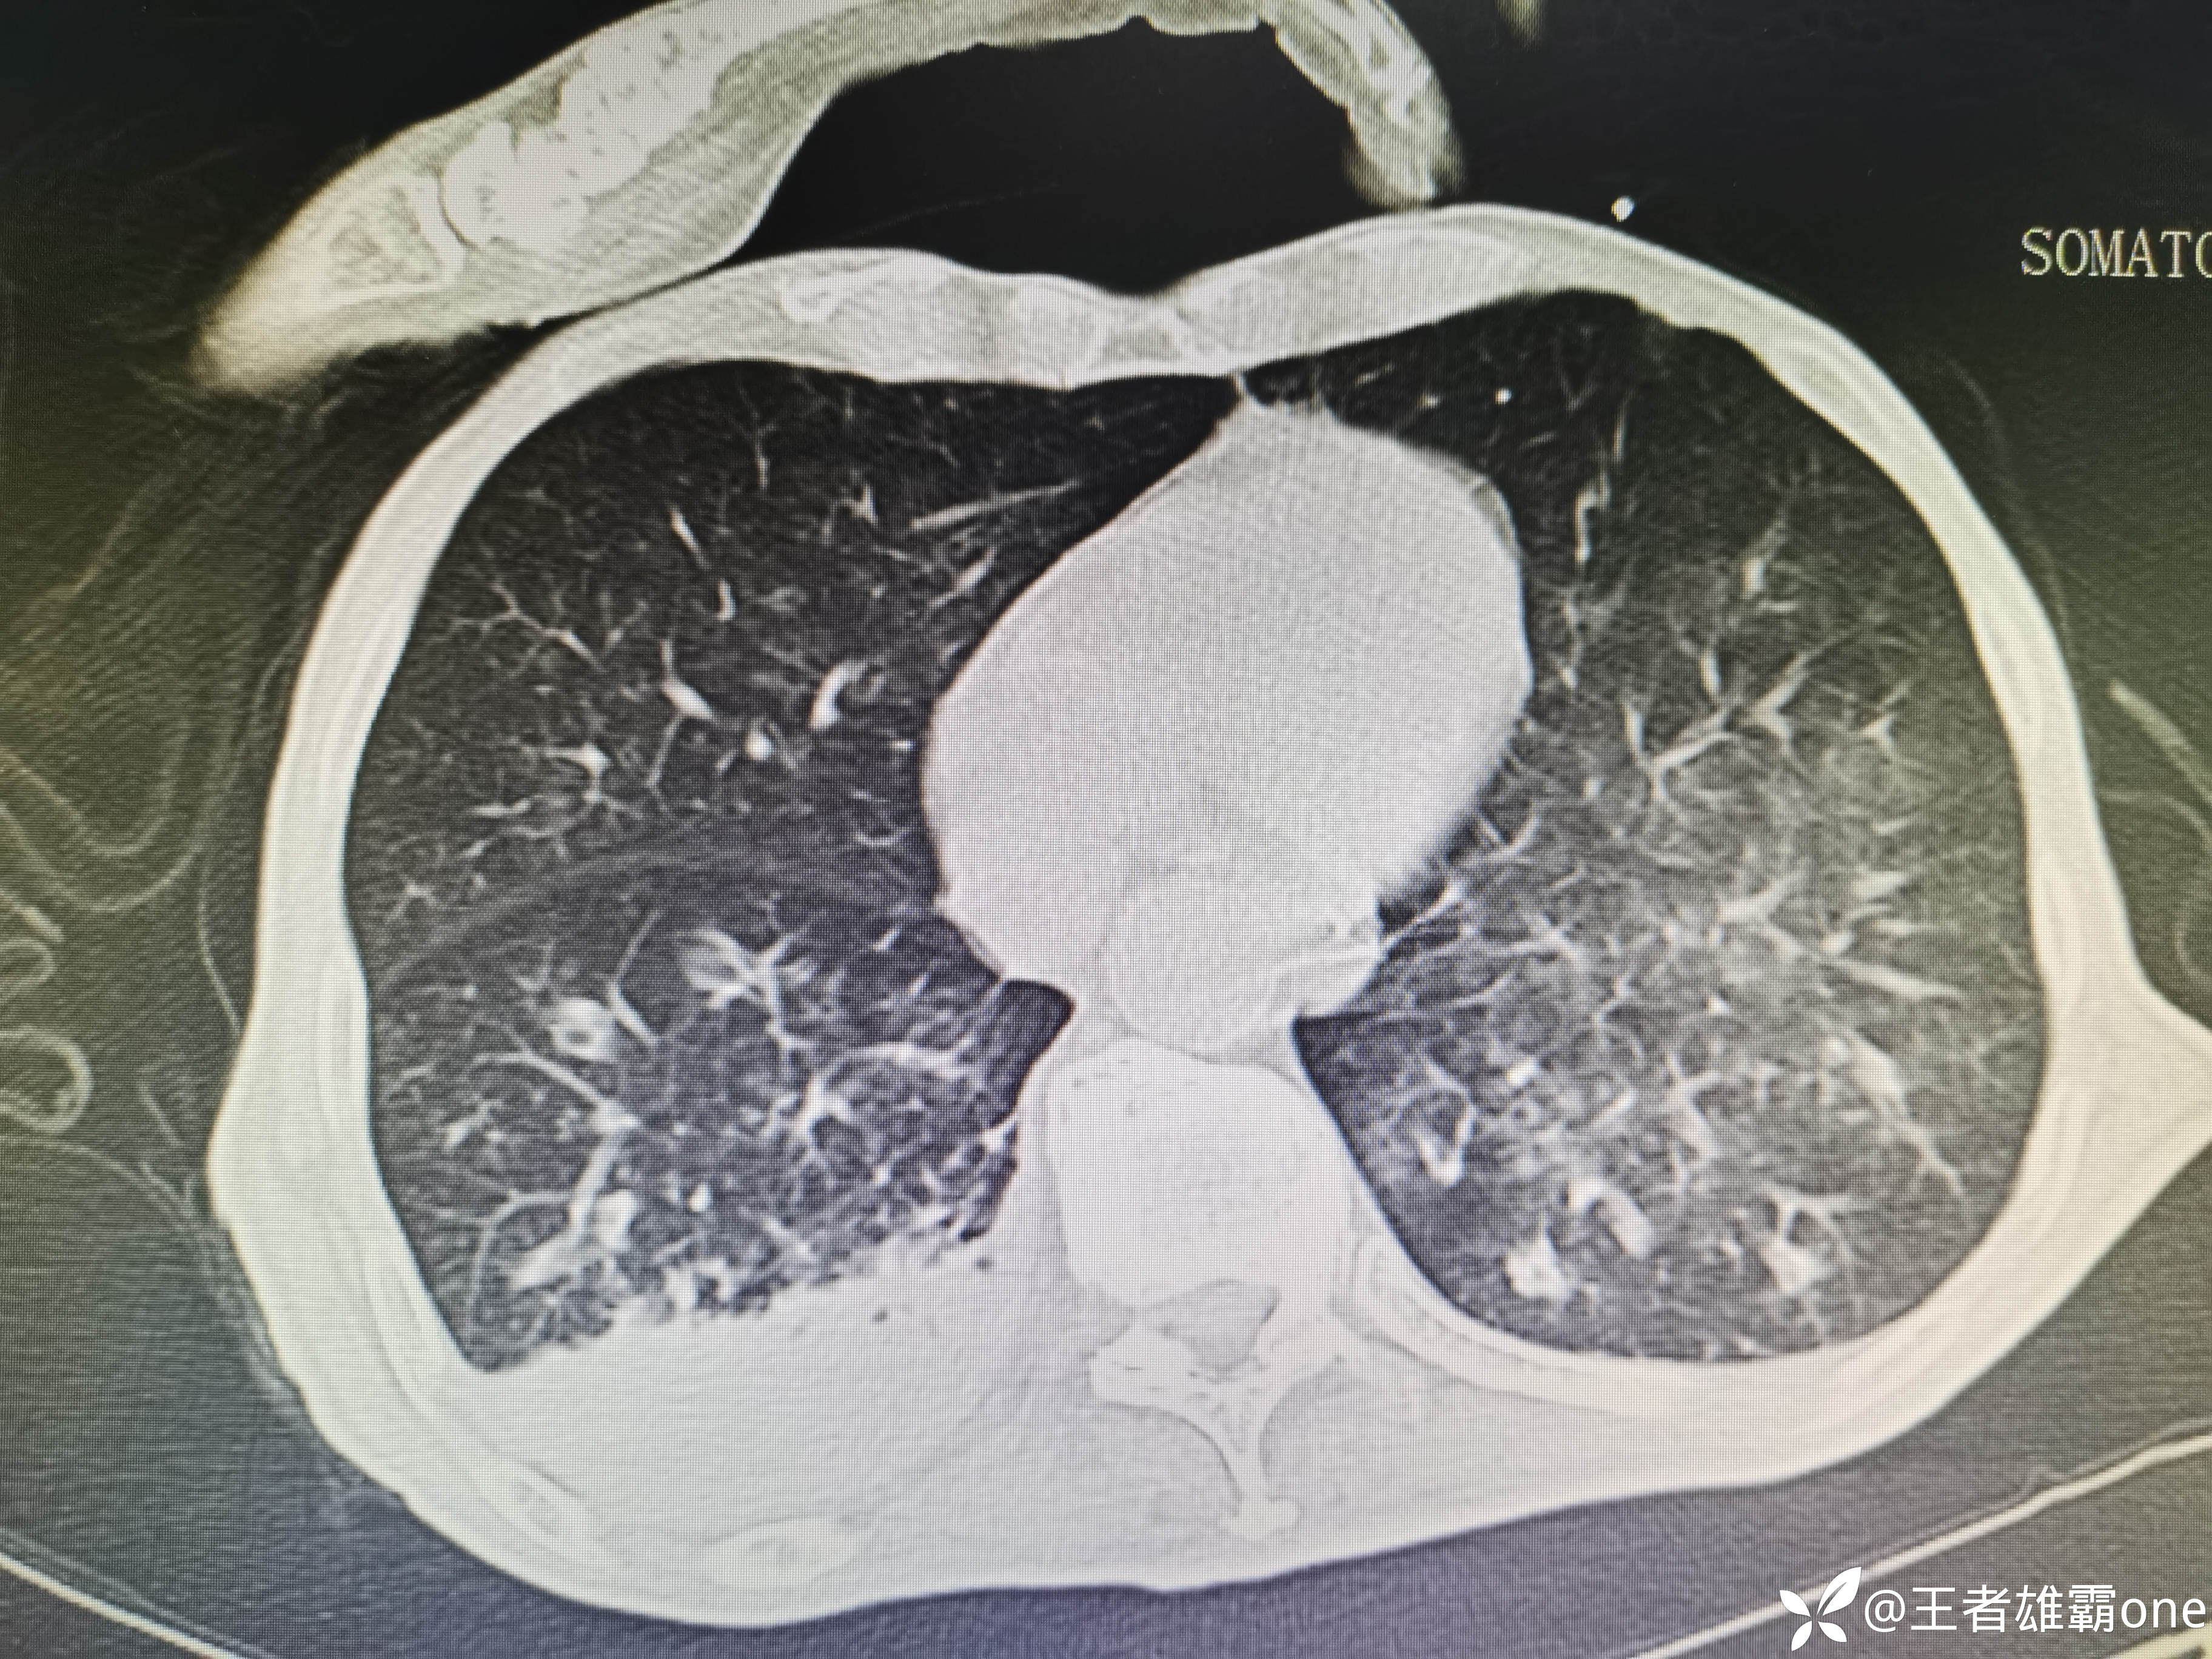

入院时胸部CT:

具体图片: